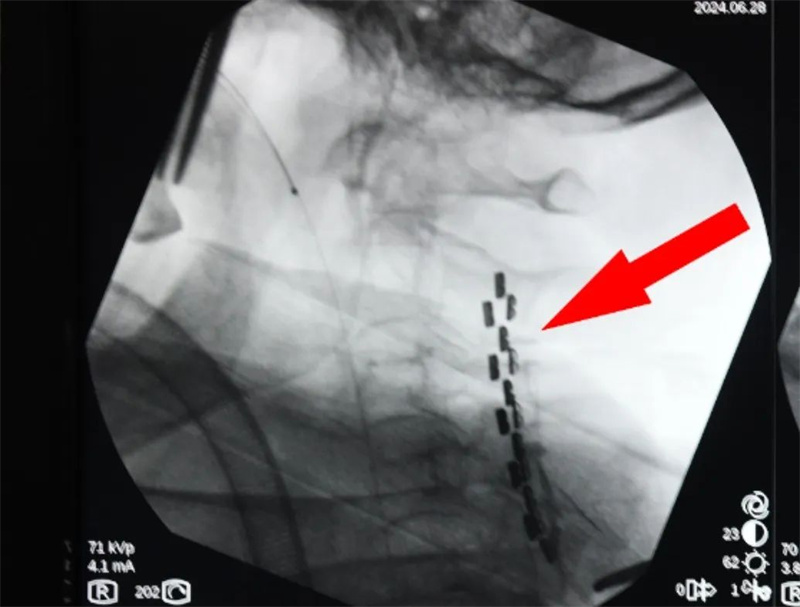

6月28日,傅楚华再次带领团队向“慢性意识障碍(昏迷)”的促醒治疗发起了挑战——脑室腹腔分流术+高颈段脊髓电刺激术再“促醒”。术后10天,顺利开机并对王奶奶进行持续神经调控管理。

傅楚华团队为王奶奶实施“高颈段脊髓电刺激植入术”

适时调整电刺激的点位、频率、电流(资料图)

“刺激的频率、时间和电流强度都可以自定义调节,白天进行刺激的时候,肌肉也会活动起来,晚上要睡觉的时候,就要调成睡眠状态。”傅楚华介绍,通过精准的程序控制,每天阶段性进行微电流的刺激,为“微意识状态”患者的促醒开辟了一条新的道路。